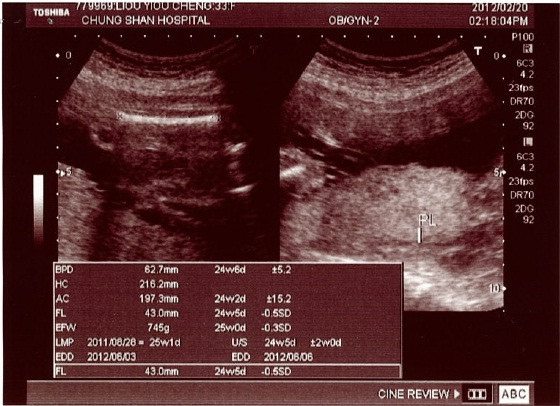

今天的超音波檢查讓我讚不絕口,執行的醫生(還是護士?)細心又仔細,逐一檢查招財的各個器官,還數了手指頭與腳指頭,總之一切的過程,有如我們先前在香港做結構性超聲波一樣詳細,而且收費又便宜,鍵哥直說早知道這時回台灣再做就好了,呵呵!

依據招財目前的體型, 判斷大約是幾周大的孩子.